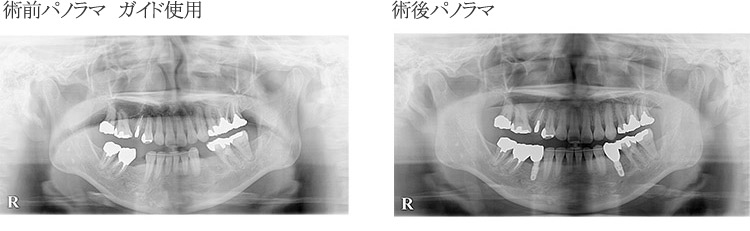

зҹӯгҒ„жҷӮй–“гҒ§жӯЈзўәгҒӘжІ»зҷӮгӮ’иЎҢгҒӘгҒҶгҒҹгӮҒгҒ«гҒҜгҖҒе…ҘеҝөгҒӘиЎ“еүҚжә–еӮҷгҒҢж¬ гҒӢгҒӣгҒҫгҒӣгӮ“гҖӮеҪ“йҷўгҒ§гҒҜдәӢеүҚгҒ«гӮігғігғ”гғҘгғјгӮҝгғјгҒ«гӮҲгӮӢгӮ·гғҹгғҘгғ¬гғјгӮ·гғ§гғігӮ’иЎҢгҒӘгҒ„гҖҒжӯҜ科еҢ»её«гҒ®жүӢгҒ®ж„ҹиҰҡгҒЁеӢҳгҒ«й јгӮӢгғ•гғӘгғјгғҸгғігғүгҒ§гҒҜгҒӘгҒҸгҖҒгӮ¬гӮӨгғүгӮ’дҪҝгҒҶгҒ“гҒЁгҒ§еҲҮй–ӢгҒҷгӮӢйғЁеҲҶгӮ’жңҖе°ҸйҷҗгҒ«жҠ‘гҒҲгҖҒгӮҲгӮҠзІҫеҜҶгҒ§й«ҳеәҰгҒӘжІ»зҷӮгӮ’е®ҹзҸҫгҒ•гҒӣгҒҰгҒ„гҒҫгҒҷгҖӮ

гӮөгғјгӮёгӮ«гғ«гӮӘгғҡгҒ«гӮҲгӮӢгӮ¬гӮӨгғүгӮӘгғҡгҒ«гҒӨгҒ„гҒҰ

е®үеҝғе®үе…ЁгҒӘгӮӨгғігғ—гғ©гғігғҲгҒ®жӨҚз«ӢгҒ®зӮәгҒ«дәҲгӮҒCTгҒ®ж’®еҪұгҖҒгӮҪгғ•гғҲдёҠгҒ§гӮ·гғҘгғҹгғ¬гғјгӮ·гғ§гғігӮ’иЎҢгҒ„гҖҒгҒқгӮҢгҒ«еҹәгҒҘгҒ„гҒҰ3Dгғ—гғӘгғігӮҝгғјгҒ§гӮөгғјгӮёгӮ«гғ«гӮ¬гӮӨгғүгӮ’дҪңгҒЈгҒҰжүӢиЎ“гӮ’иЎҢгҒ„гҒҫгҒҷгҖӮ гҒқгҒ®зөҗжһңгҖҒиҝ…йҖҹгҒӢгҒӨжӯЈзўәгҒӘгӮӘгғҡгҒҢеҸҜиғҪгҒЁгҒӘгӮҠгҒҫгҒҷгҖӮгҒҫгҒҹзё«еҗҲгҒ®еҝ…иҰҒгӮӮгҒӘгҒ„гҒҹгӮҒгҖҒдҪ“гҒёгҒ®иІ жӢ…гӮ’жҠ‘гҒҲгӮӢгҒ“гҒЁгҒҢгҒ§гҒҚгҒҫгҒҷгҖӮ